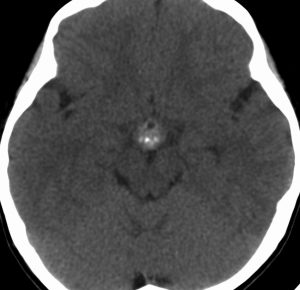

10歳くらいから身長の伸びが遅くなって,12歳で食欲低下と体重減少がありました。左のMRIはガドリニウム造影MRIで,視床下部と下垂体を侵す神経下垂体ジャーミノーマです。CTでは小さな石灰化(白い点)がみえます。CT検査は不必要なものでした。